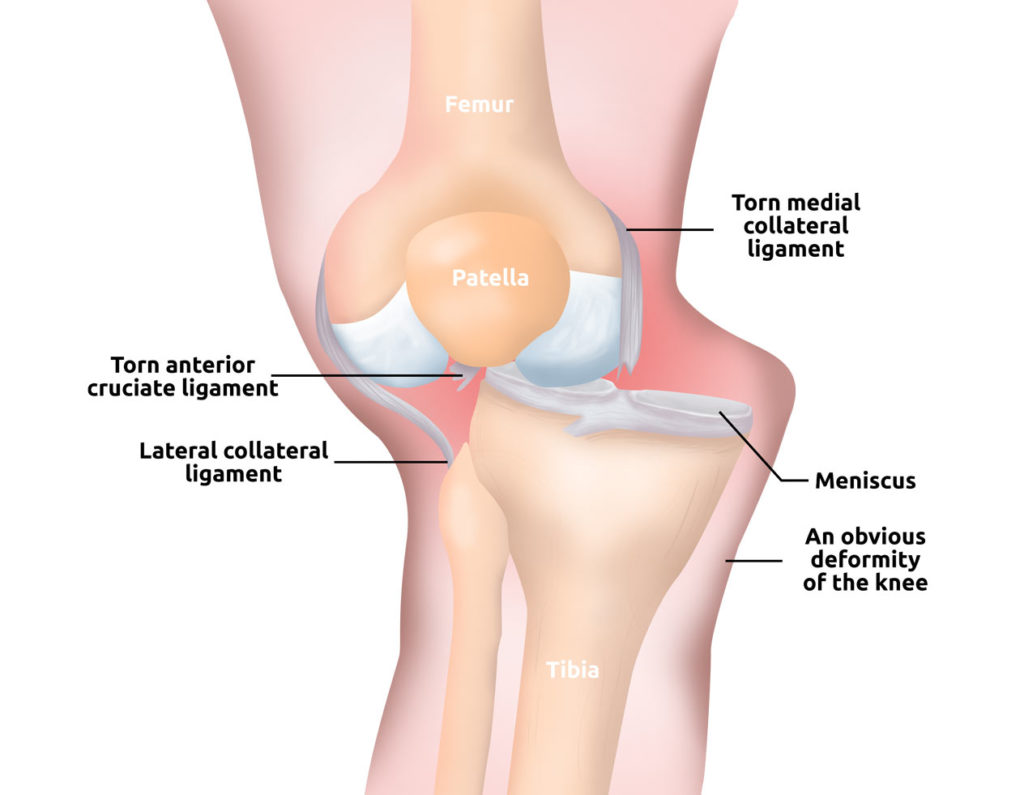

WHAT DOES KNEE DISLOCATION MEAN?

A knee dislocation occurs when the bones that form the knee are out of place. In the result, the ligaments are torn and knee is unstable.

Together with knee dislocation, the meniscus and articular cartilage are damaged. Immediately after injury, the kid feels the pain and joint is swollen. The leg is deformed and motion is limited.

In this case, the knee should be immobilized in professional kid lower limb immobilizer AM-TUD-KD.

- knee dislocation

- knee sprain

- knee instability

- ACL, PCL, MCL and LCL injuries

- meniscus tears and injuries

- patellar fracture

- patellar dislocation